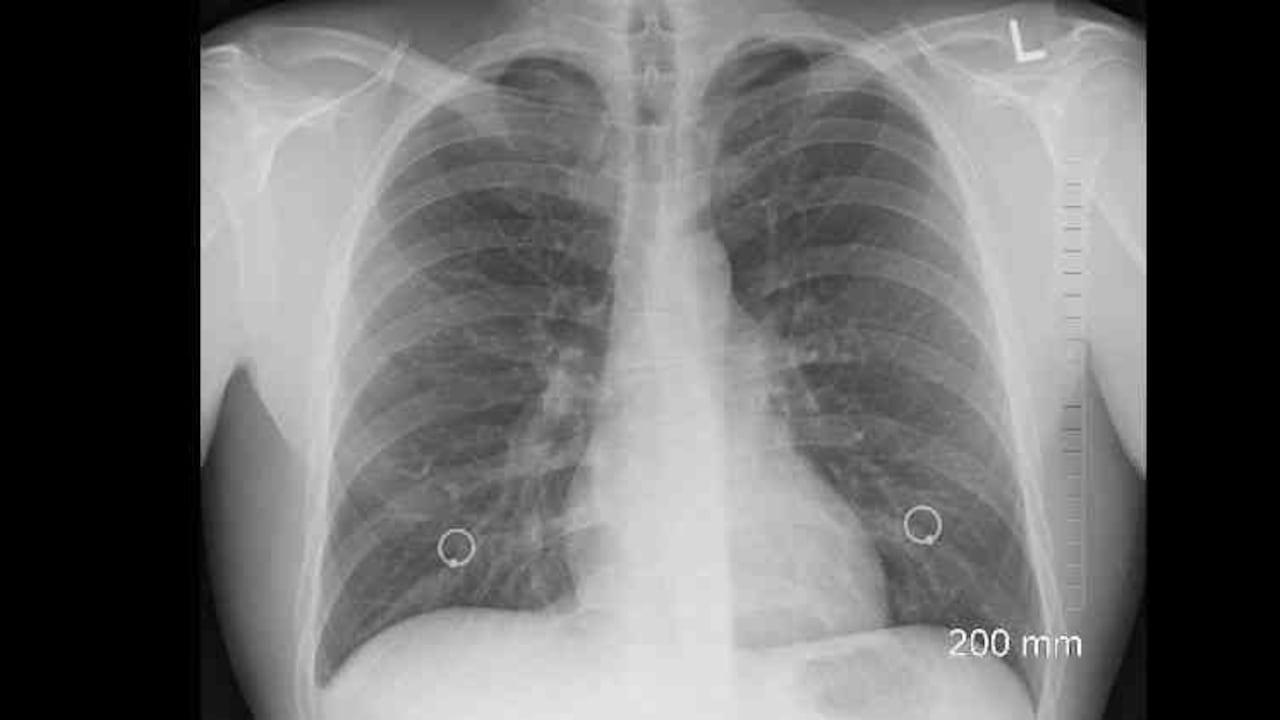

C.M: Primero, con la aparición de los síntomas y simultáneamente hay que hacer un tac de tórax que nos permite hacer la identificación radiológica. Después, hay que hacer unas pruebas de función pulmonar para hacer el seguimiento.